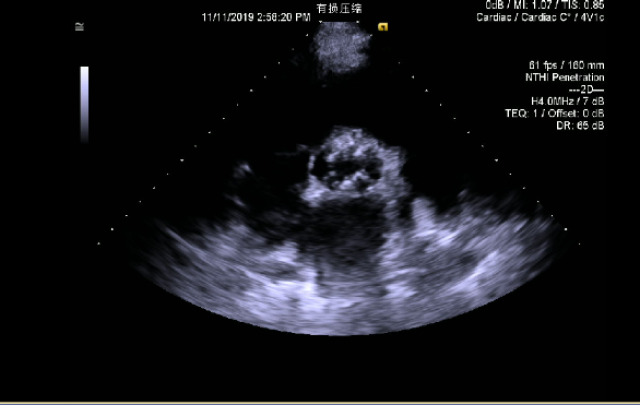

超声心动图:

左心增大,室间隔增厚,左室心尖部小室壁瘤形成,大小约15x12mm;主动脉瓣病变,二叶瓣不除外,重度狭窄(跨瓣压差58mmHg),轻-中度关闭不全;二尖瓣钙化,轻-中度关闭不全;三尖瓣中-大量反流,肺动脉收缩压增高,估测肺动脉收缩压约为52mmHg。主动脉瓣Vmax:510cm/s,左室射血分数减低,左室舒张末径: 59 mm,左室射血分数: 24 %。